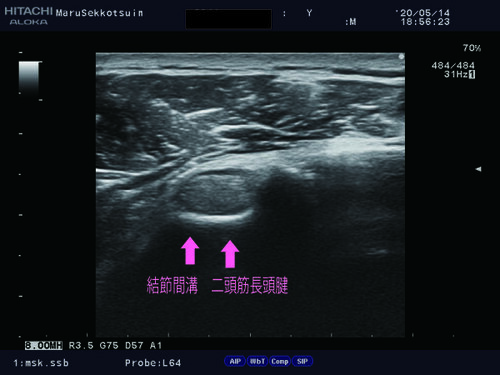

いつものようにしっかり問診、視診、触診後、確認の為、エコー検査。

上腕二頭筋長頭腱2.jpg上腕二頭筋長頭腱3.jpg

上の写真を診て頂いてお察しの方もいらっしゃると思いますが、

結果は「上腕二頭筋長頭筋腱移行部断裂」でございました。